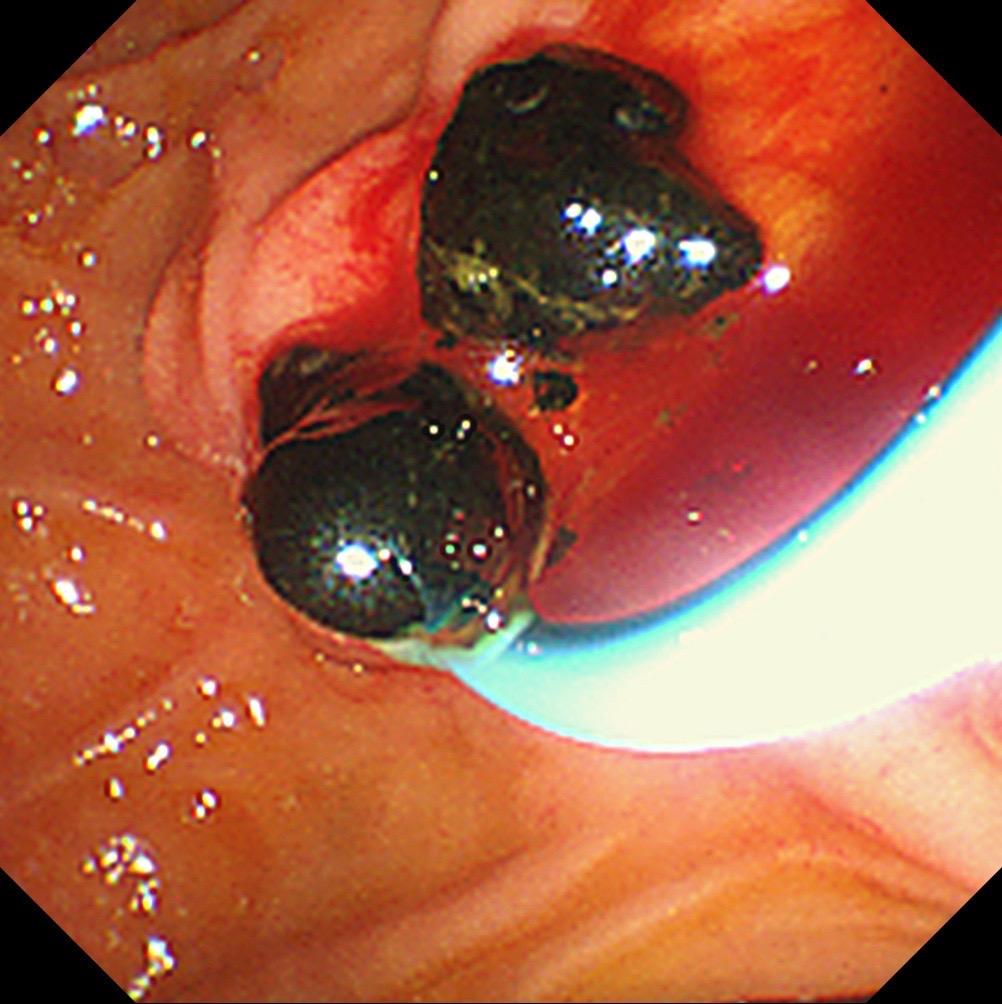

地狱级间质瘤切除!胃角大部分胃壁外生长 近4CM的间质瘤,难切也难缝...